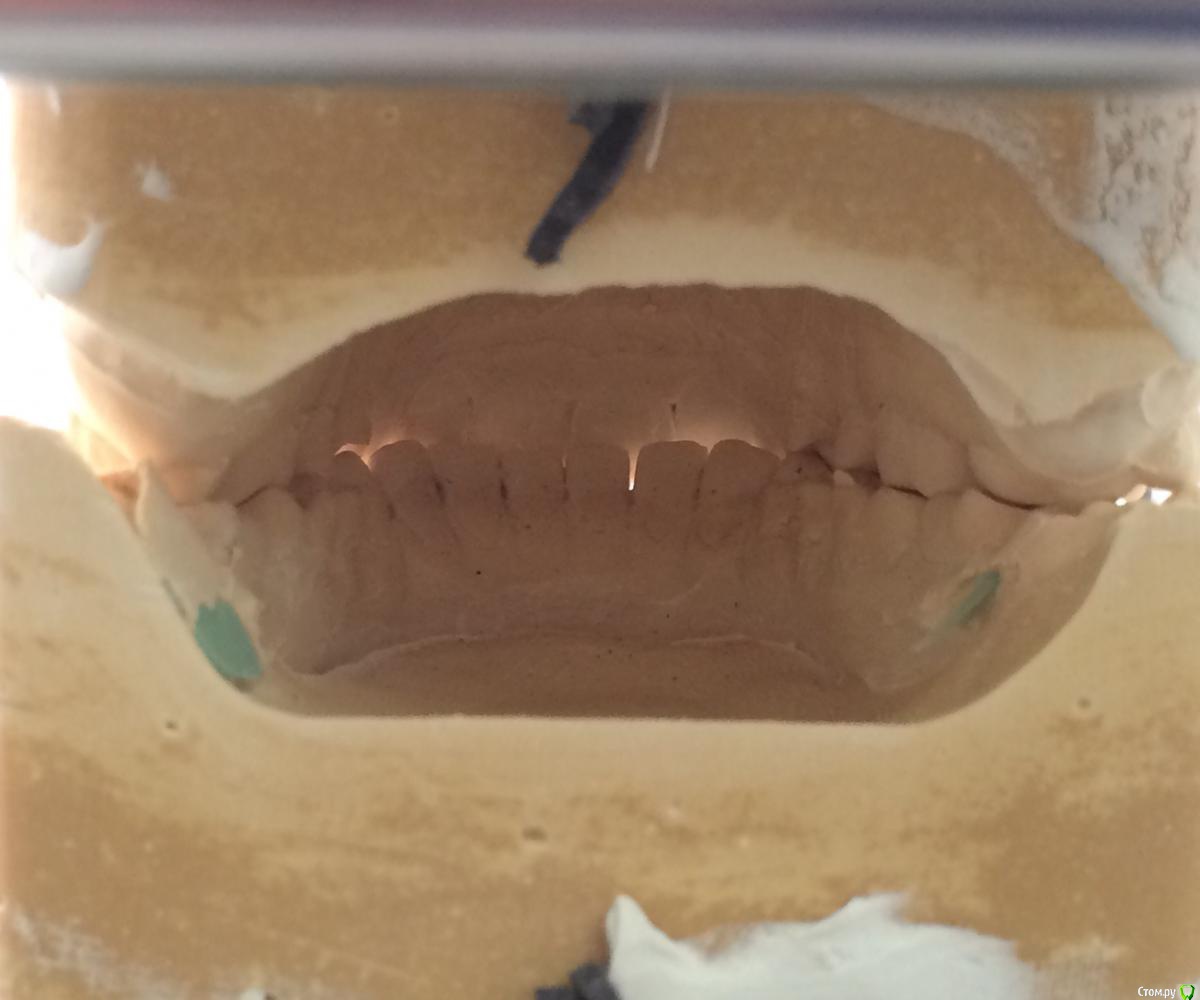

Larnary Опубликовано 28 июля, 2015 Поделиться Опубликовано 28 июля, 2015 (изменено) Добрый день!Ко мне обратилась пациент 1988 гр с жалобой на стираемость зубов и постоянные сколы пломб.Объективно небная поверхность верхних резцов стерта до дентина. Окклюзионная стираемость жевательной группы зубов.Прошу помочь с выявлением причины такой стираемости зубов и оптимальноно метода лечения Изменено 28 июля, 2015 пользователем Larnary Ссылка на комментарий

Larnary Опубликовано 28 июля, 2015 Автор Поделиться Опубликовано 28 июля, 2015 (изменено) Видно окклюзионнык интерференции в области 37 и 47.На днях удален 38 и дальше будут удалены остальные восьмерки. На ТРГ мне видится небольшая ретрузия верхних резцов,дистальный прикус. Так же левпя окклюзионная кривая более выраженная,чем правая Изменено 28 июля, 2015 пользователем Larnary 1 Ссылка на комментарий

PLAY Опубликовано 28 июля, 2015 Поделиться Опубликовано 28 июля, 2015 Загипсовано в центральном соотношении? Ссылка на комментарий

Larnary Опубликовано 28 июля, 2015 Автор Поделиться Опубликовано 28 июля, 2015 (изменено) в центральной окклюзии Изменено 28 июля, 2015 пользователем Larnary Ссылка на комментарий